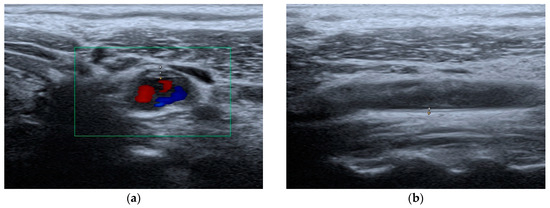

4.3. Musculoskeletal Ultrasound

| AT | 6 (35.29) | 3 (17.65) | 5 (29.41) | 5 (29.41) | 5 (29.41) | 1 (5.88) |